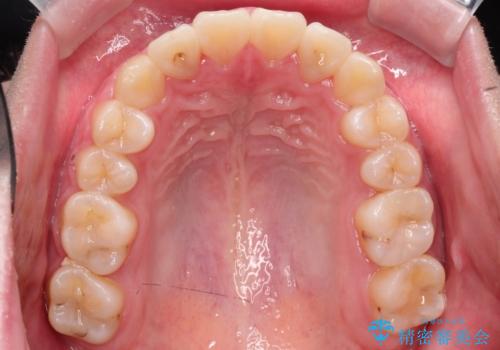

【インビザライン】前歯の凸凹を非抜歯で治療

- 前歯の凸凹を主訴の来院されました。

奥歯を後ろの方に移動させるために矯正用のアンカースクリューを使いながら治療をおこないました。

患者さんの都合により、マウスピースの装着時間が不足したため、途中からワイヤーにて治療を行いました。

インビザラインは20時間以上の装着は必要となるため、患者さんによってはワイヤーの方が向いていることがあります。